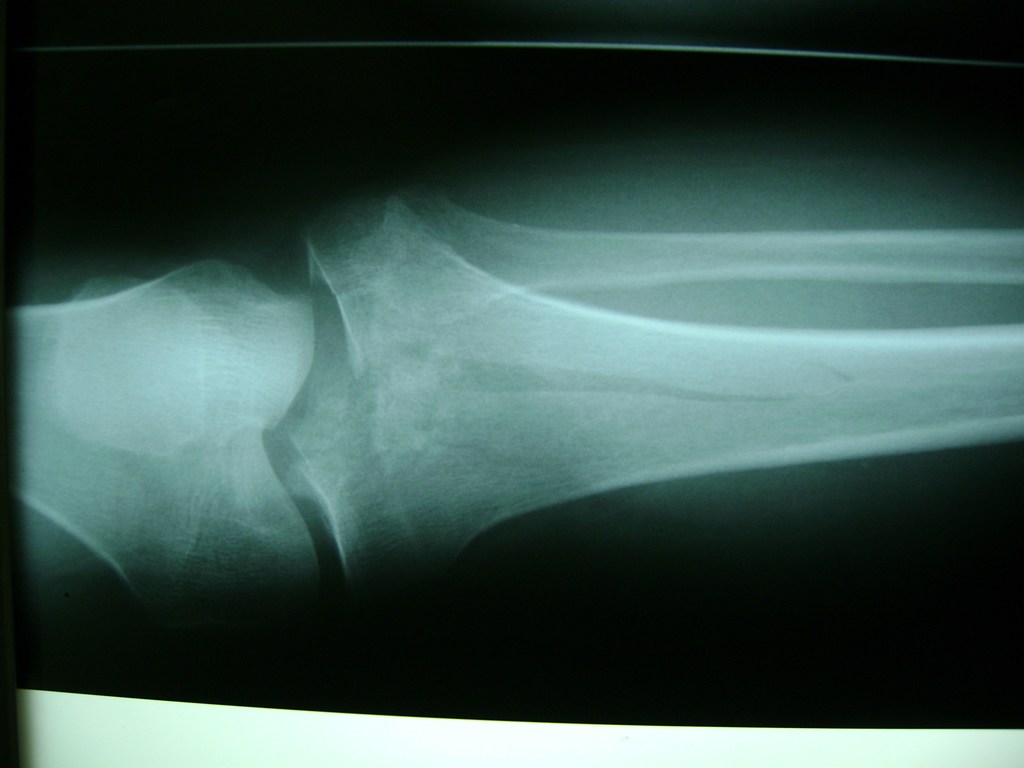

Cirugía de Fémur - Rodilla

La artroscopia de rodilla es un cirugía en el cual la estructura interna de la articulación es examinada ya sea para realizar un diagnostico o para realizar un tratamiento, este procedimiento se realiza utilizando un instrumento parecido a un pequeño tubo llamado artroscopio.